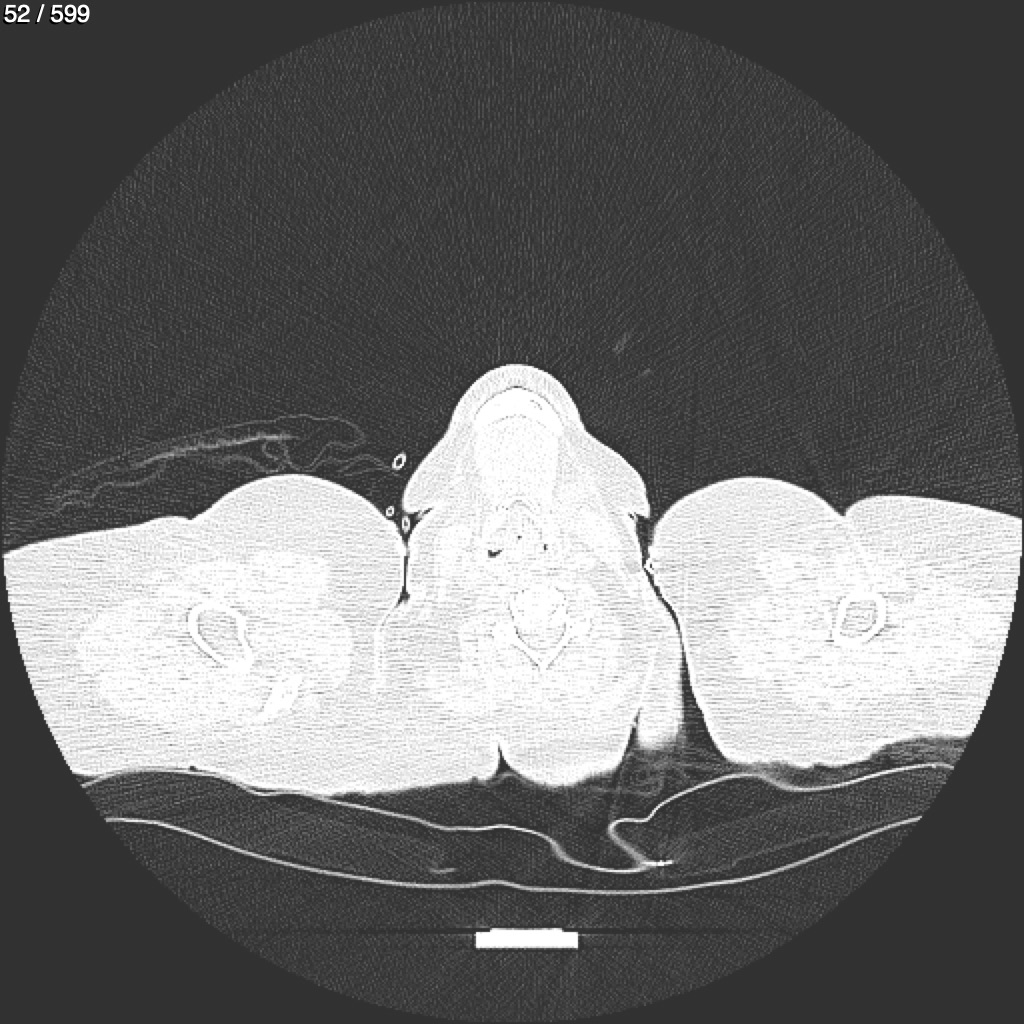

Home G​l​o​r​i​a​ ​G​l​a​d​y​s​ ​B​e​a​s​l​e​y​ ​-​ ​T​ó​r​a​x​ ​T​o​r​a​x​_​S​i​m​p​l​e​ ​(​A​d​u​l​t​o​)